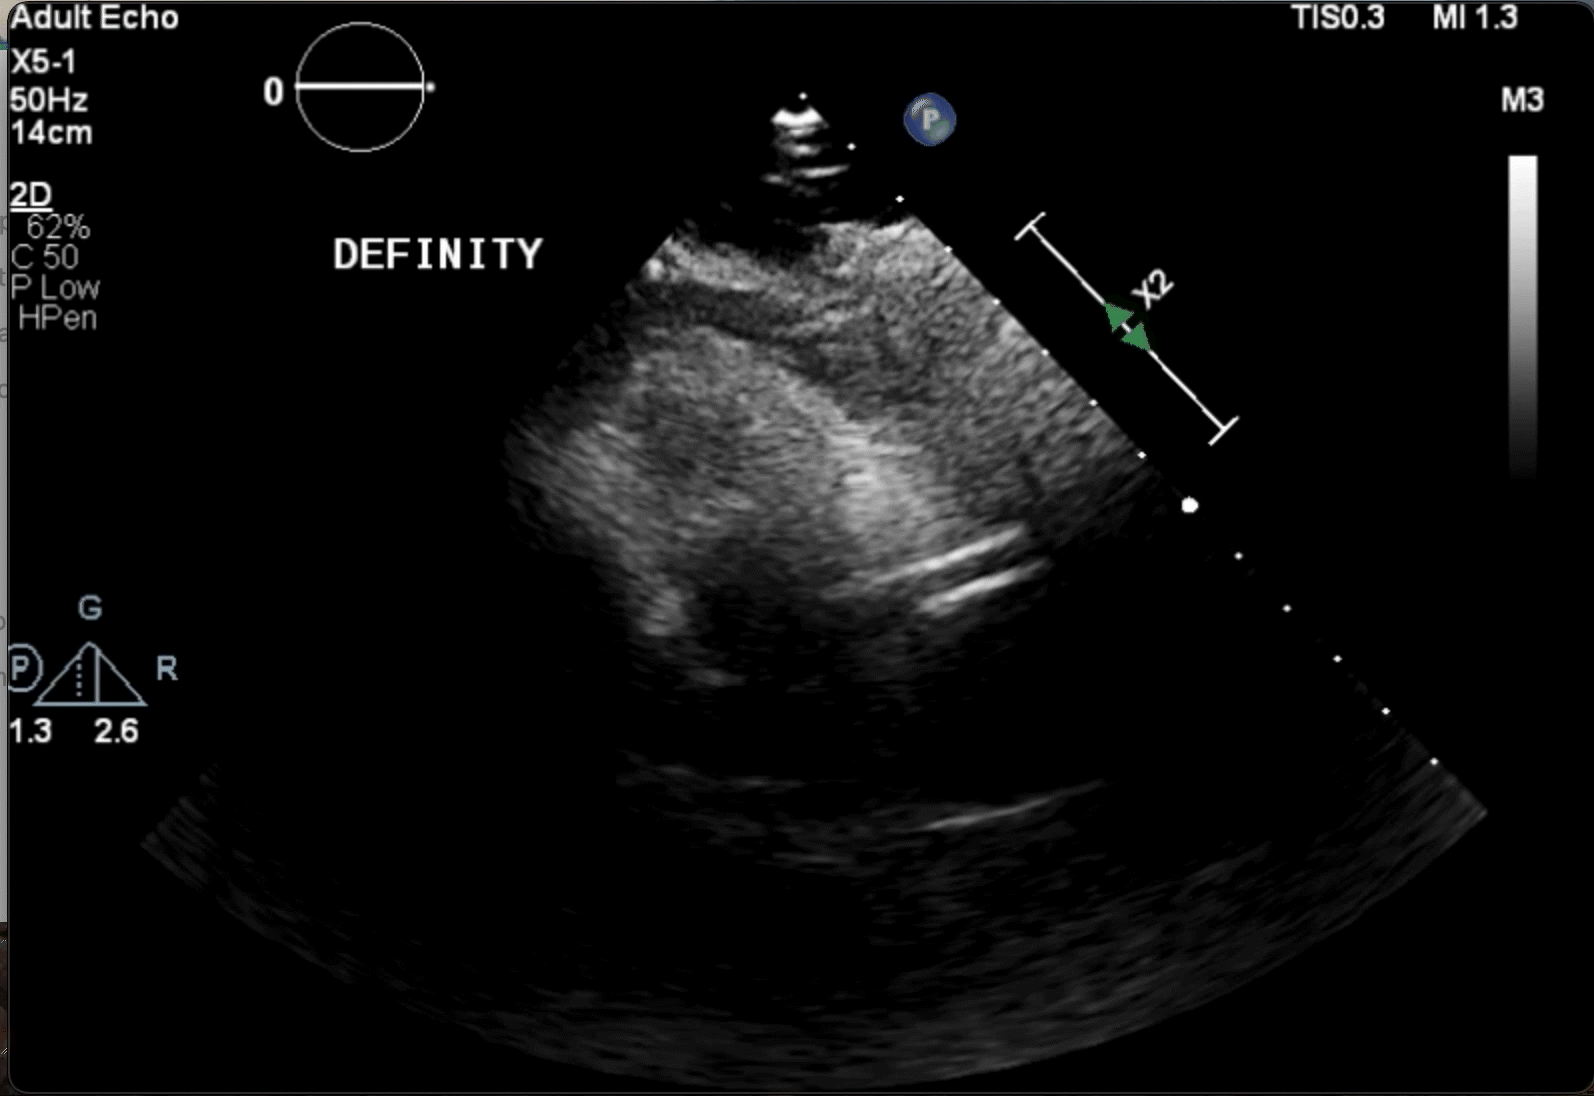

Figure 1. Initial angiography with severe stenosis of the proximal left anterior descending (blue arrow) (A). After intervention, a coronary artery perforation is seen in the distal vessel (blue arrow) (B). Transthoracic echocardiography showing the left ventricle and right ventricle (C). CEE after intracoronary injection of the UEA, the UEA is seen filling the right ventricle while notably absent from the pericardium (D).

After balloon tamponade, continued extravasation was present on angiography. CEE was performed with an intracoronary injection of an UEA. The UEA was seen filling the cardiac chambers, but no pericardial effusion was seen and there was no UEA identified filling the pericardial space (Figures 1C and 1D, Video 2). Together with the angiographic finding, we determined the perforation was likely into a coronary vein. No further intervention was performed. The patient remained hemodynamically stable and was later discharged without significant events.